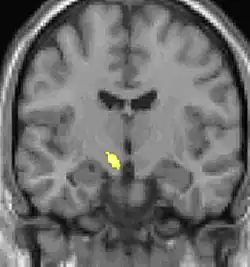

| La tomographie par émission de positons (TEP) montre les zones du cerveau étant activées durant la douleur | ||

Les images par tomographie à émission de positron indiquent les régions du cerveau qui sont activées lors de la douleur, par rapport aux périodes sans douleur. Elles montrent les régions du cerveau qui sont toujours actives durant la douleur en jaune/orange (appelé "matrice-douleur"). La zone au centre (dans les trois vues) est spécifiquement activée uniquement pendant la crise. Les photos sur la ligne du bas (effectuées par VBM) montrent les différences structurelles entre les patients souffrant d'AVF et des personnes saines : seulement une partie de l'hypothalamus est différente[50],[51].